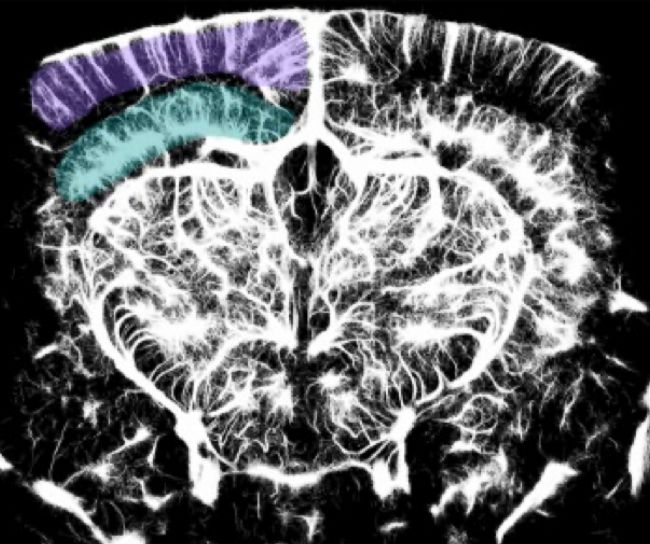

圖2 Tarantini 教授團隊使用 Iconeus One 上的 ULM 技術獲得的小鼠腦血管圖譜示例 。該圖像顯示了皮層(紫色)和海馬(藍色)區域 ,并展示了該技術覆蓋范圍的分辨率、靈敏度和深度 。經作者許可轉載[2]